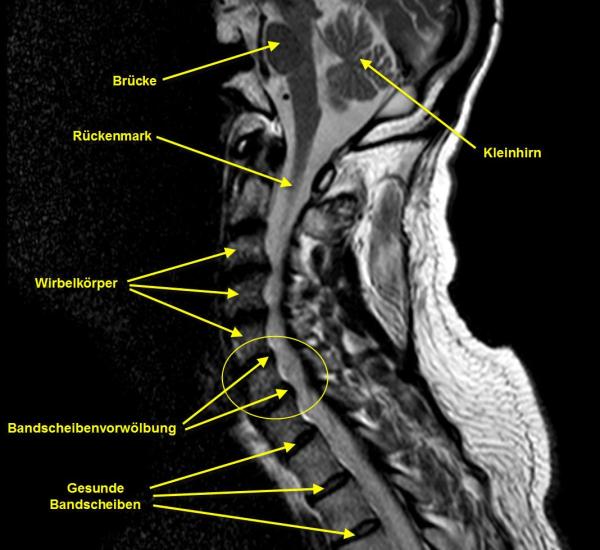

Diese Methode ist jedoch nicht unbedingt von Erfolg gekrönt. Insbesondere dann nicht, wenn nicht mehr nur von einer Bandscheibenvorwölbung, sondern von einem echten Bandscheibenvorfall gesprochen werden muss. Der Unterschied liegt im Grad des Bandscheibenaustritts. Eine Vorwölbung ist die noch eher alternativ behandelbare Variante einer Bandscheibendisfunktion, während bei einem ausgeprägten Bandscheibenvorfall eine baldige Operation angezeigt ist, da jedes Zuwarten die Gefahr erhöht, dass ein Teil der Bandscheibe von den Wirbelsäulenknochen abgeschert wird, was eine umfangreiche, teils kritische Operation nötig macht.

Ein Bandscheibenvorfall muss nicht immer voll ausgeprägt sein. Bereits eine Bandscheibenvorwölbung kann extreme Schmerzen verursachen. Mit der Nucleosplasty steht den Ärzten jedoch ein ausgezeichnetes, minimalinvasives Verfahren zur Verfügung, hier zu helfen.

Wölbt sich eine Bandscheibe vor, so trifft das Gewebe oft auf einen Nerv, der dadurch einen Dauerschmerzreiz erzeugt.